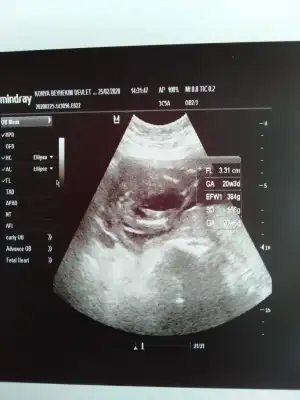

S.a Ikra meyra Ikra meyra cnm ultrason resmini alınca sana aticaktm bugüne kısmetmiş ben biseyy anlamadm ya görüntü net değil ya da ben tecrubesizim sana zahmet bakar msn sence cinsiyet ne bugün sırf cinsiyet için farkli doktora gittim 🤭☺️🤔

S.a Ikra meyra Ikra meyra cnm ultrason resmini alınca sana aticaktm bugüne kısmetmiş ben biseyy anlamadm ya görüntü net değil ya da ben tecrubesizim sana zahmet bakar msn sence cinsiyet ne bugün sırf cinsiyet için farkli doktora gittim 🤭🤔